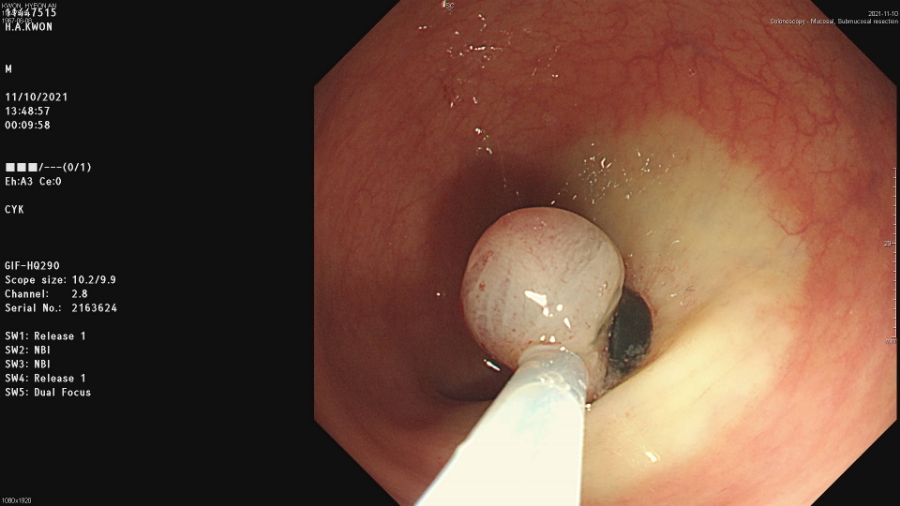

원인을 찾으려고 차움건강검진센터를 예약해서 대장내시경, 위내시경, 초음파검사를 하면서 직장종양을 발견하고 강남 차병원에 가서 직장점막하종양제거수술을 받고

차병원에서 찍은 CT, 초음파, 대장, 위카메라 CD를 보여드리며 담석증 소견과 신장 10cm 정도의 물집을 제거하도록 원장.

성모병원 외과전문의가 있는 바로 초음파실로 찾아가 진료 시작 후 10분 정도 초음파로 구석구석

구석구석을 살펴보고 진료실로 오라고 해서 진료실에 가서 결과를 듣기 시작했어요.

말하면서 담석염입니다담석증으로 사용하는 게에 있는 돌이 몇 번이나 빠져 나오기 때문에 담낭벽에 염증을 일으키는 병입니다.